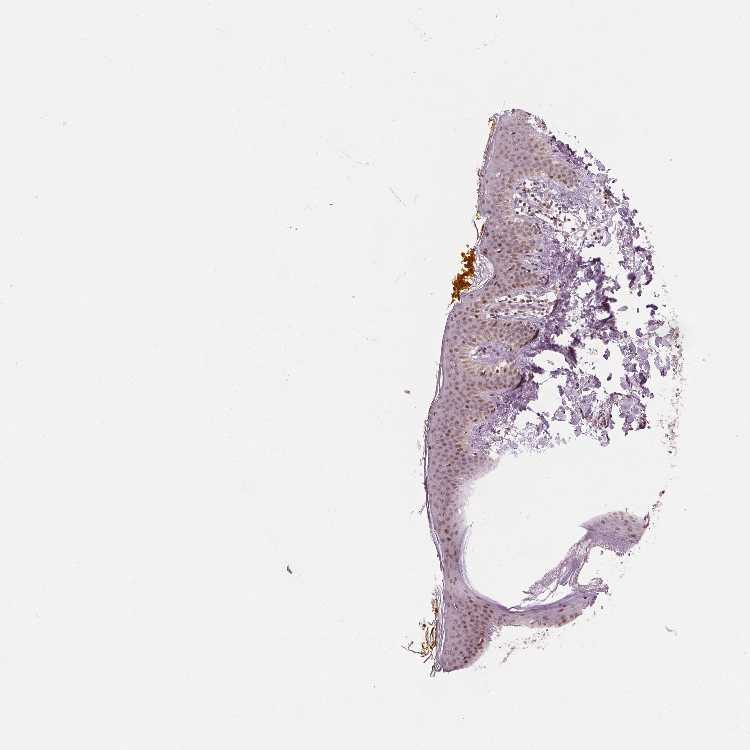

SKIN 2 - Antibody stainingi

Antibody staining in the annotated cell types in the current human tissue is reported as not detected, low, medium, or high, based on conventional immunohistochemistry profiling in selected tissues. This score is based on the combination of the staining intensity and fraction of stained cells.

Each image is clickable and will lead to virtual microscopy that enables deeper exploration of all samples and also displays staining intensity scores, fraction scores and subcellular localization as well as patient and tissue information for each sample.

Antibody HPA066832

Epidermal cells Medium